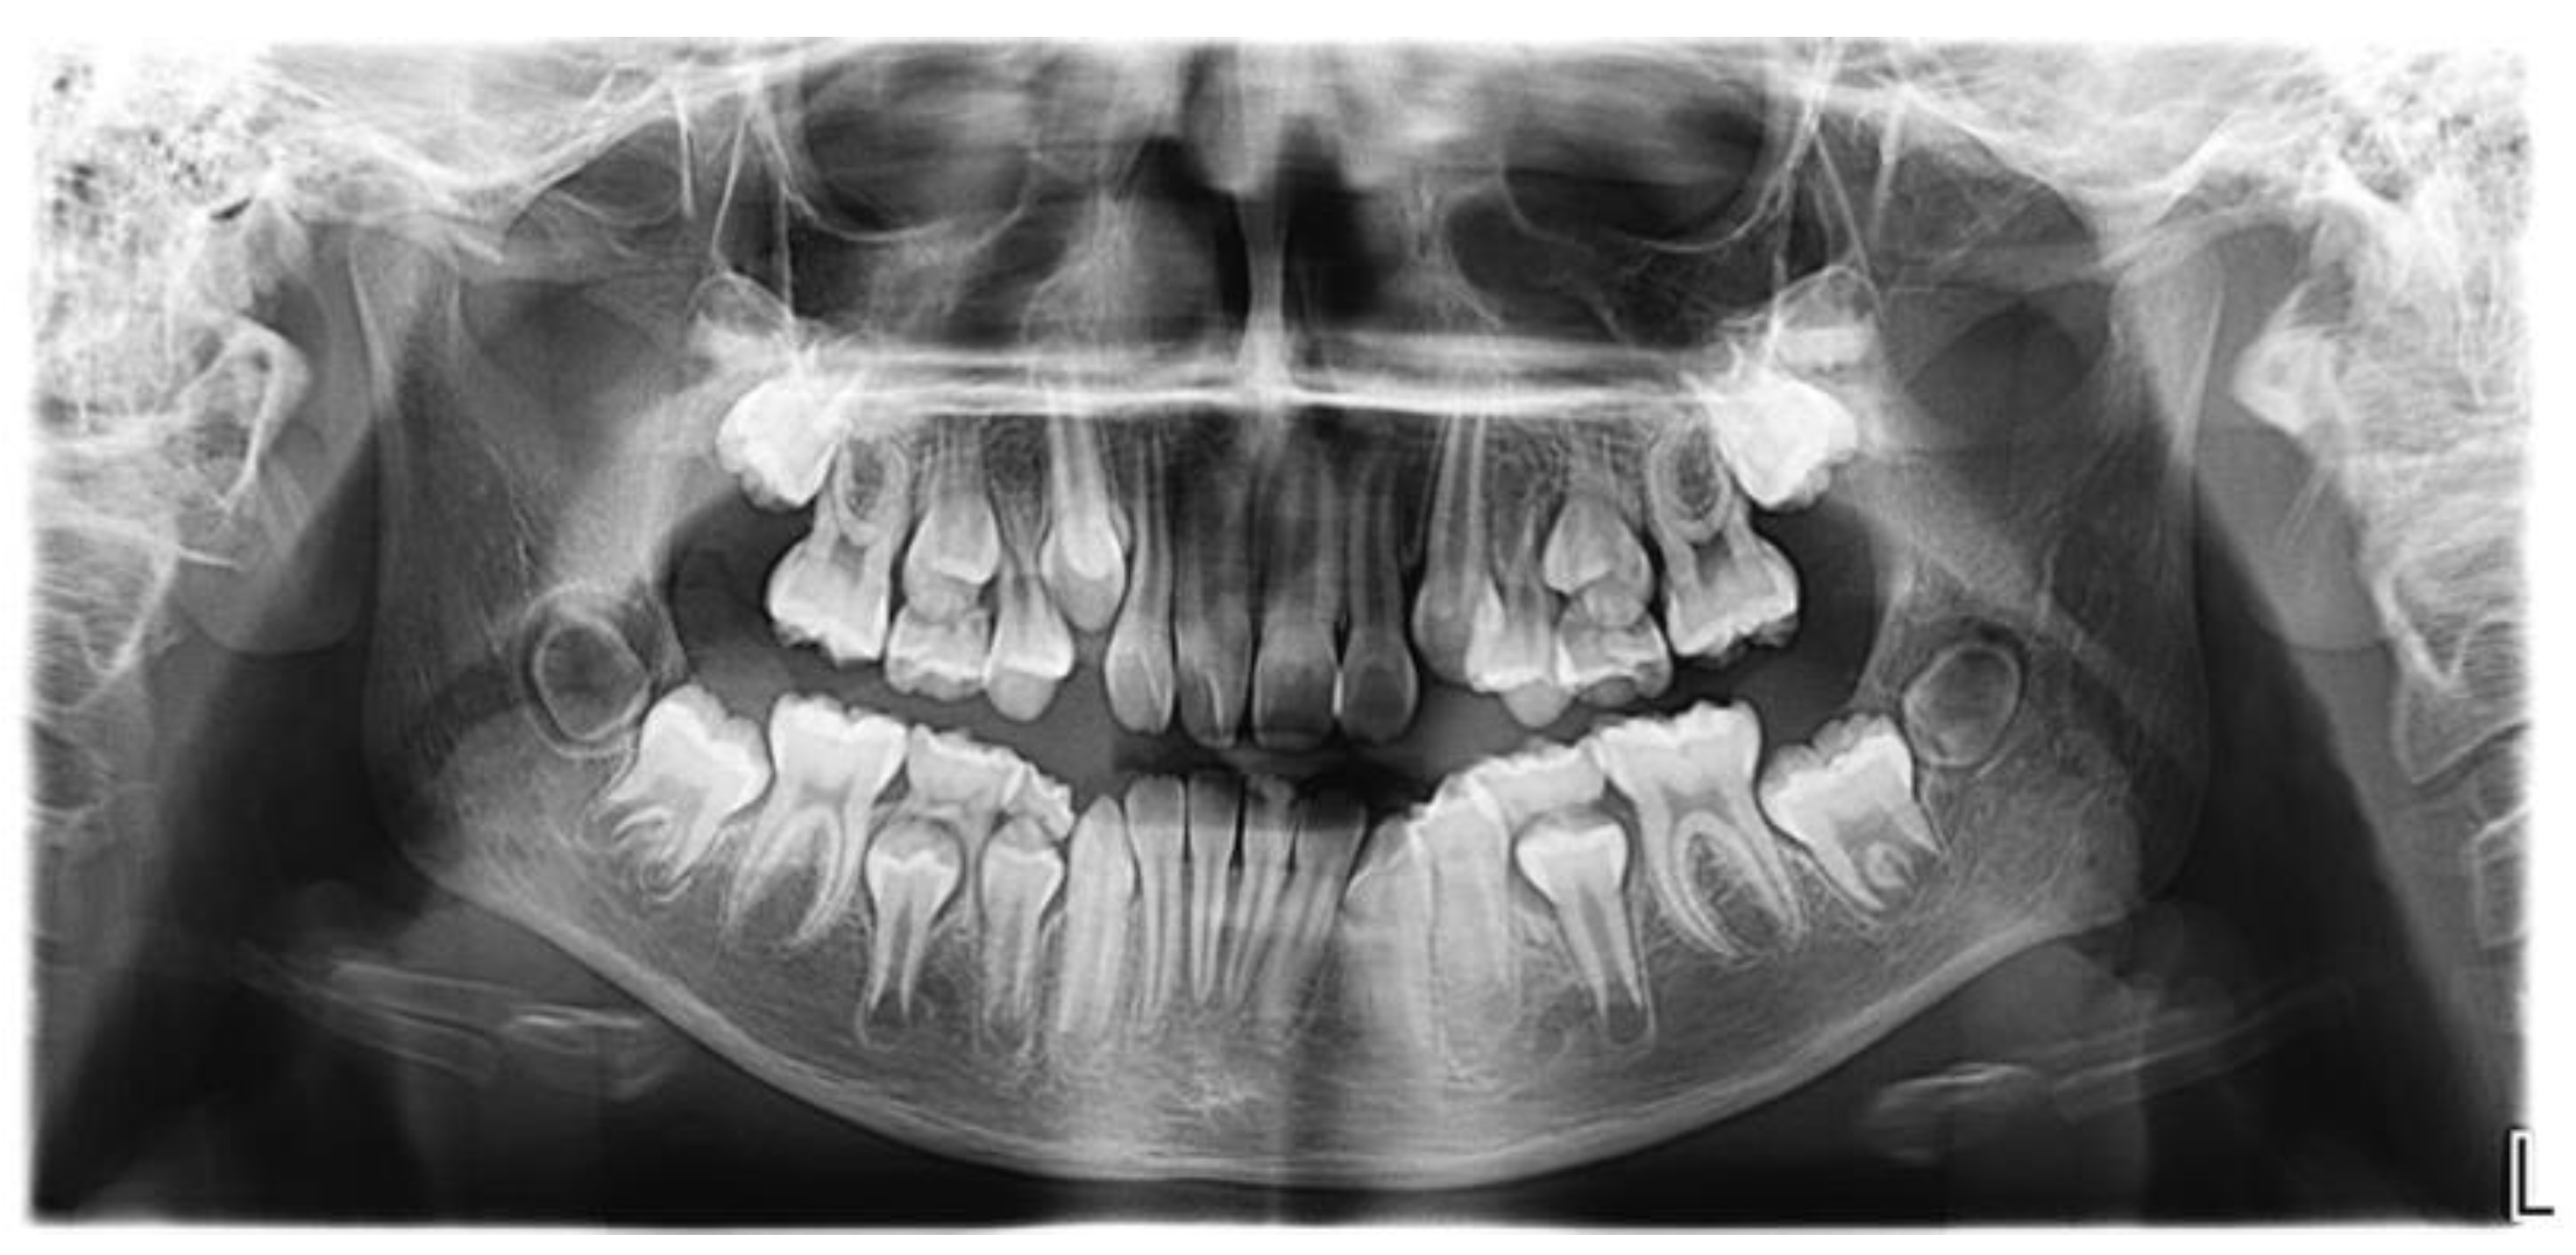

2. Case Report